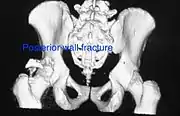

Posterior wall fracture as seen on 3-D CT scan

Posterior wall fracture fixed with screws and plate